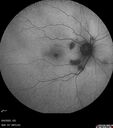

Last additions - Cotton wool spots following Cario-pulmonary bypass 58 year old man The patient had emergency thoracotomy about 3 weeks ago he had an aortic dissection with a root aneurysm. It had dissected down to the iliacs. The patient had a thoracotomy and aortic valve replacement and large aortic graft. He did well post-op and then he noticed when he got out of the hospital that the right eye was worse. The right eye had been weaker than the left even after LASIK in the early 2000s. Over the last 7 days now that he has noticed that the right eye is getting better each day. He is on coumadin and will be on it for 3 months. He noticed 10 days ago that there was some graying in the right eye which is now getting a little bit better.

Cotton Wool Spots following cardio-pulmonary bypass28 viewsThe patient had emergency thoracotomy about 3 weeks ago he had an aortic dissection with a root aneurysm. It had dissected down to the iliacs. The patient had a thoracotomy and aortic valve replacement and large aortic graft.Mar 15, 2026